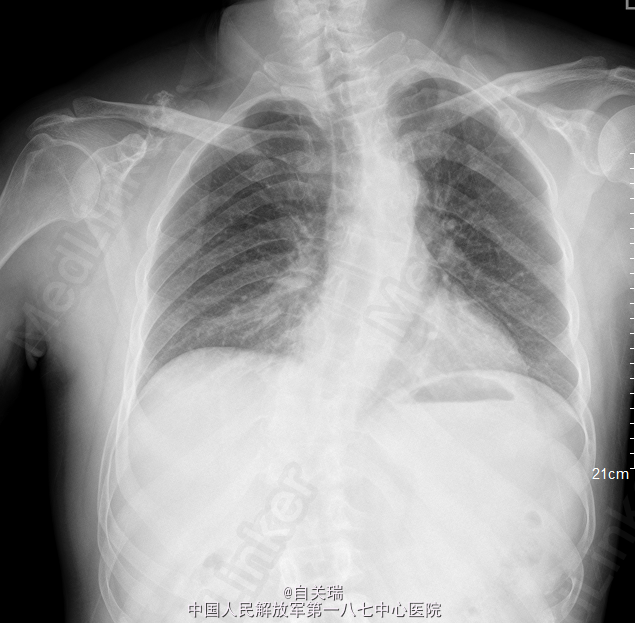

患者,男,49岁,因“反复右肩疼痛1年,发现右肩肿块1周”入院。 患者1年前无明显诱因下右肩部疼痛,无活动不利,无麻木.

右肩胛骨冈上方可触及一肿块,大小约2*3cm,局部压痛(+),皮色皮温正常,右肩活动正常,末梢血供及感觉功能存在。MRI提示:右肩胛冈上缘占位,骨软骨瘤可能。